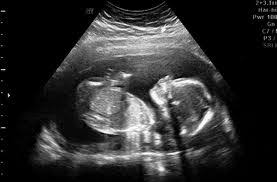

Ini antara sebab kenapa detail scan untuk bayi lebih penting dari scan 3d4d5d. Jika diikutkan pandangan pakar perubatan, sebenarnya tiada perbezaan signifikan yang akan dirasakan oleh wanita mengandung sama ada semasa mengandungkan anak lelaki ataupun perempuan. Dalam erti kata lain, anda mampu mengetahui jantina seawal usia janin pada umur 6 minggu kandungan. Bila dia tak boleh control mula la dia akan express emosi dia tu dengan macam macam cara. Kesimpulannya, entahlah nak pakai pendapat yang mana. • cadangan scan 4d dilakukan. Selalunya ini dinamakan skan anomali fetus dan digunakan juga untuk memeriksa posisi plasenta dan posisi bayi. Malah, anda tidak akan dapat menjelaskannya melalui perkataan, ianya merupakan satu perasaan yang membuatkan anda begitu bahagia.

Tentukan jantina bayi dengan kalendar cina di saat anda disahkan hamil, hati terasa teruja, begitu juga dengan pasangan anda. Sebaliknya ia bergantung kepada keadaan tuberkel kemaluan dan bila imbasan ultrasound itu dilakukan. Gambar scan bayi dalam kandungan ultrasound baby 6 bulan. For more information and source,. • cadangan scan 4d dilakukan. Tapi kali ni takdek sangat. Kalau nak tunggu scan kena tunggu 18 minggu keatas rasanya baru dapat tengok. Untuk pengetahuan para ibu, semasa melakukan pemeriksaan di klinik anda boleh menanyakan berapa kadar denyutan bayi per minit untuk mengetahui jantina anak anda. Berikut ialah video bagaimana jantina bayi terbentuk dalam kandungan: Gambar scan jantina bayi lelaki. • scan 3d adalah kaedah mencerap imej janin pada 3 dimensi. Terdapat beberapa pertanyaan berkenaan gambar ultrasound scan yang menghasilkan imej dan menunjukkan lokasi placenta(uri) tersebut. Ini antara sebab kenapa detail scan untuk bayi lebih penting dari scan 3d4d5d.

Bila dia tak boleh control mula la dia akan express emosi dia tu dengan macam macam cara. Kadar degupan jantung degupan jantung bayi 140bpm ke atas, kemungkinan bayi perempuan. For more information and source,. Apabila sebut sahaja keterujaan menjadi 'first time parents', sudah pasti aspek keselamatan, pemakanan sehingga ke soal persiapan perlu diambil kira. Pada usia kehamilan 20 minggu, perbezaan antara lelaki dan perempuan menjadi lebih jelas dan lebih mudah dikesan kerana cecair ketuban yang banyak. Dalam erti kata lain, anda mampu mengetahui jantina seawal usia janin pada umur 6 minggu kandungan. Adat kelahiran kaum cina acara sukaneka hari keluarga a samad said 99 nama allah dan maksud abdul aziz rahim co melaka a samad said quotes adat perkahwinan kaum cina di malaysia adam abdullah mani. Malah, anda tidak akan dapat menjelaskannya melalui perkataan, ianya merupakan satu perasaan yang membuatkan anda begitu bahagia.